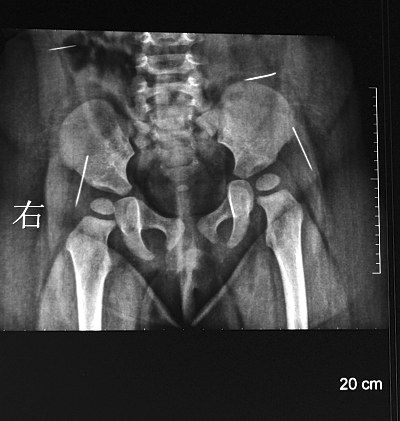

萌萌手術(shù)前拍攝的CT片顯示,4個(gè)白亮的針狀物分布在腰部和臀部兩側(cè)。據(jù)主刀醫(yī)生、淮安市婦幼保健院小兒科副主任陳衛(wèi)兵介紹,4根縫衣針長度從1.5厘米到約2厘米不等,都沒有針鼻兒。臀部的兩根針有可能觸及坐骨神經(jīng),腰部的那根眼看就要移動(dòng)到肝臟位置。

陳衛(wèi)兵介紹,手術(shù)難度很大,為準(zhǔn)確定位萌萌體內(nèi)的4根針,他邊看X光片,邊電話聯(lián)系放射科主任,參照早晨剛拍的CT片來定位。取出4根針后,他發(fā)現(xiàn)最后取出的那根比X片上顯示的短了半截,隨后他又將斷針找了出來。